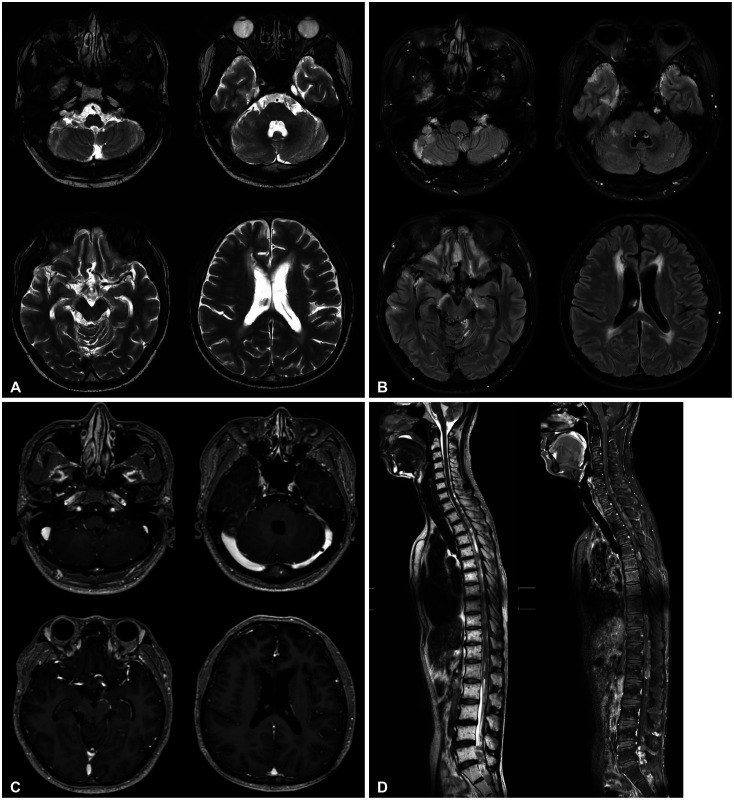

Ependymoma is a rare adult tumor that originates from ependymal cells of the central nervous system, primarily occurring in the cerebral ventricles or the central canal of the spinal cord. In this paper, we report a case of extensive leptomeningeal seeding of ependymoma of a 39-year-old male patient, in whom the tumor was found incidentally after head trauma. The MRI exhibited diffuse leptomeningeal infiltrative lesions along with bilateral multiple cerebral sulci, basal cisterns, cerebellopontine angle, cerebellar folia. It also showed multinodular enhancing T1 low T2 high signal intensity lesions along the whole spinal cord. After the tumor biopsy at right temporal lesion, pathologic diagnosis was classic ependymoma (WHO grade 2). The patient has undergone radiation therapy and chemotherapy, and is currently maintaining a stable condition two years after surgery. This report suggests that when considering the differential diagnosis of extensive lesions both in the intracranial and intraspinal space, ependymoma should also be considered.